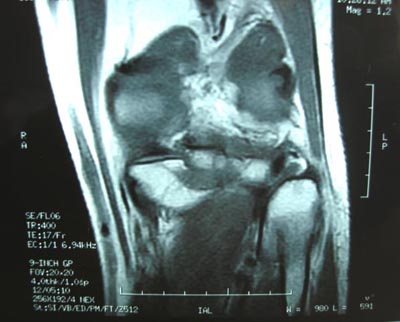

男,45。骑摩托车摔伤左膝肿痛三天,浮髌(+),活动受限。请大家看看片子有问题吗?

标题: 现将mri结果公布

手术证实是后交叉韧带胫骨附着处撕脱骨折。